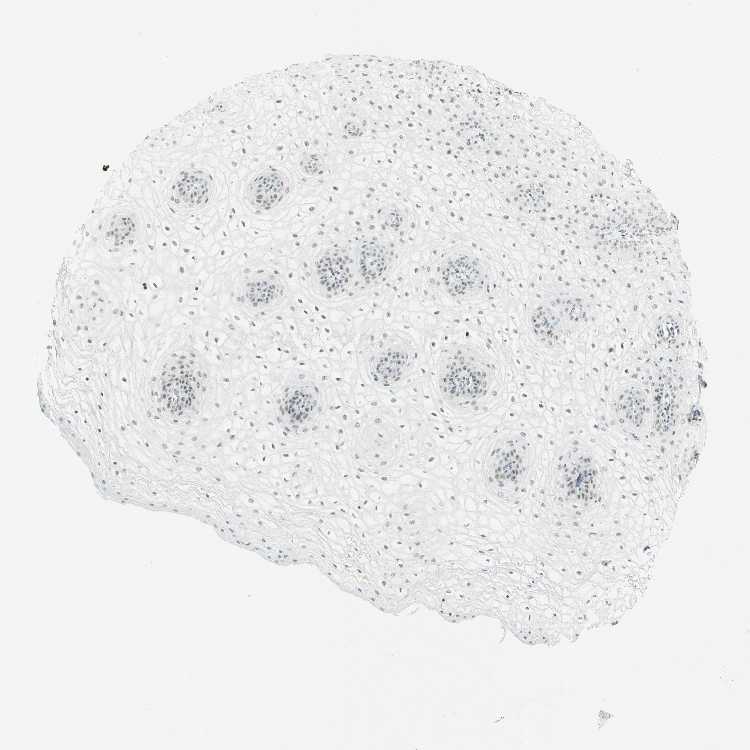

VAGINA - Antibody stainingi

Antibody staining in the annotated cell types in the current human tissue is reported as not detected, low, medium, or high, based on conventional immunohistochemistry profiling in selected tissues. This score is based on the combination of the staining intensity and fraction of stained cells.

Each image is clickable and will lead to virtual microscopy that enables deeper exploration of all samples and also displays staining intensity scores, fraction scores and subcellular localization as well as patient and tissue information for each sample.

Antibody CAB010235

Squamous epithelial cells Low